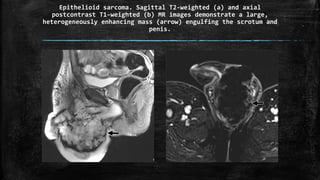

Epithelioid sarcoma. Sagittal T2-weighted (a) and axial

postcontrast T1-weighted (b) MR images demonstrate a large,

heterogeneously enhancing mass (arrow) engulfing the scrotum and

penis.

Epithelioid sarcoma. SagittalT2-weighted (a) and axial postcontrast T1-weighted (b) MR images demonstrate a large, heterogeneously enhancing mass (arrow) engulfing the scrotum and penis.